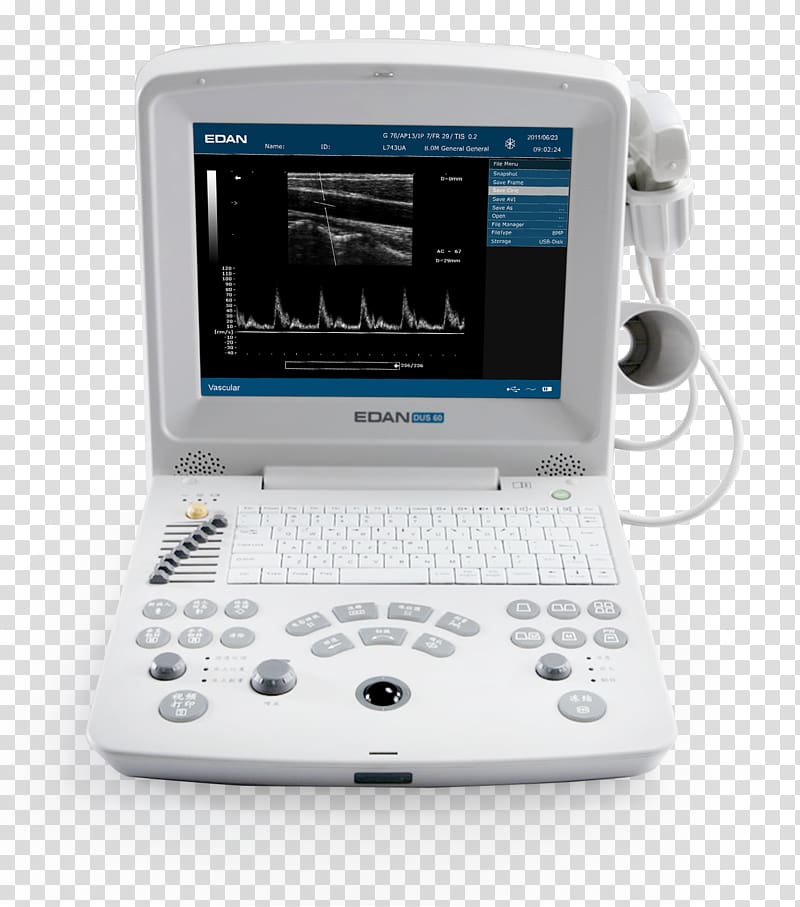

Ultrasonography Portable Ultrasound SonoScape Medical Corp Medical

www.freepik.esUltrasonography Ultrasound Medical Imaging Electrocardiography Mindray

www.freepik.esUltrasonography Ultrasound Medical Imaging Electrocardiography Mindray

www.hiclipart.comimaging electrocardiography ultrasound mindray ultrasonography others medical transparent clipart background hiclipart

www.hiclipart.comimaging electrocardiography ultrasound mindray ultrasonography others medical transparent clipart background hiclipart